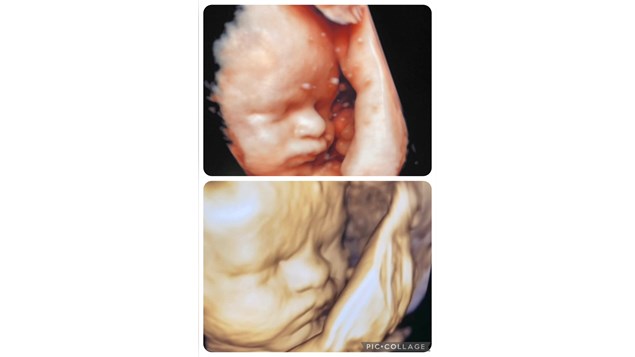

Denne fine pige er til termin - fødslen kan ske når som helst.

Hun trives i mors mave. Men fordi der er konstateret en del fostervand, kan der være flere problematikker at tage hensyn til :

Heldigvis ser hun fin ud ved kontrol og der er taget normale blodprøve på mor. Så baby har 'fri leg' lidt endnu.

God fødselsdag meget snart fine pige